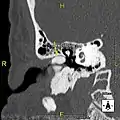

- Exostosis in ear canal